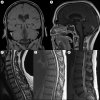

Ewing sarcoma (ES) is an aggressive, high-grade neuroectodermal neoplasm that frequently manifests in children and young adults. Although ES without osseous involvement most commonly involves paravertebral regions of the spine, it very rarely presents as a primary intracranial tumor. This report discusses a unique presentation of an adult extraosseous ES arising from the pineal region with extension into the third and fourth ventricles and multiple drop metastases to the spine. This case demonstrates the application of current chemotherapeutic and adjuvant management and offers insight into possible treatment modalities for metastasis in an atypical extraosseous ES involving the brain and spine.